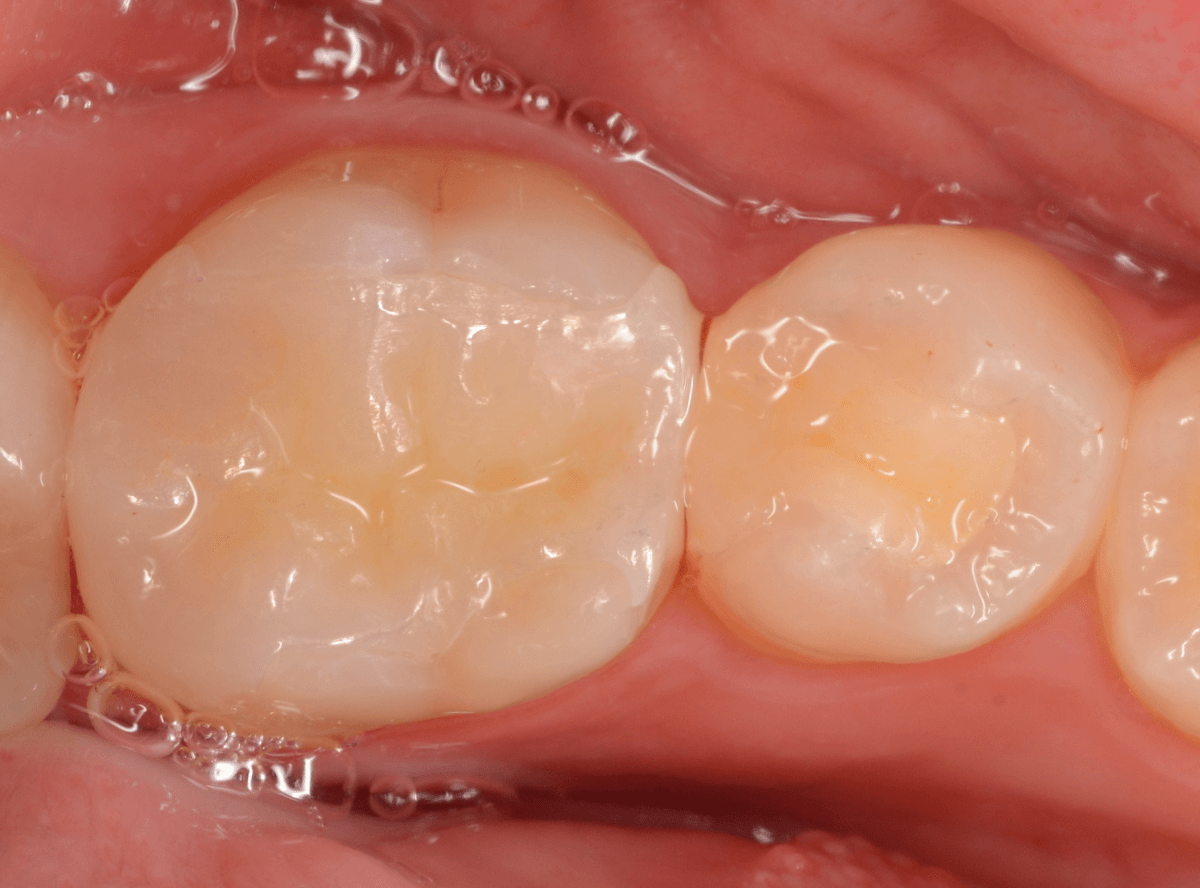

さて、しばらく経過観察後、幸い症状もありませんでしたので、最終修復に入ります。

ここで、患者さんはセラミック修復を希望されましたので、奥歯をジルコニア・インレー、手前をE-MAXインレーを製作しました。

最終setした状態です。

set後も症状なく、患者さんにも、満足していただける仕上がりになりました。

| 治療回数 | 3回 |

| 治療期間 | 1ヶ月 |

| 費用 | E-MAX・インレー (50,000円) ジルコニア・インレー (70,000円) +保険治療費用など |